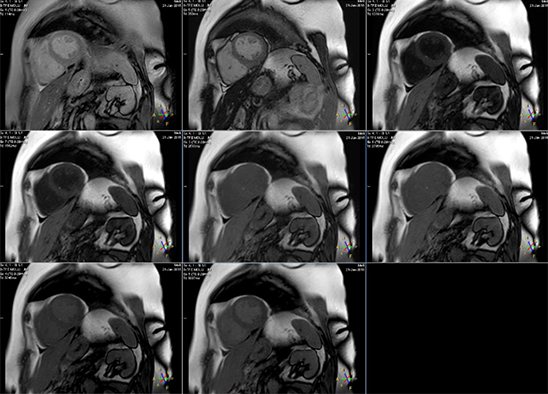

За счет синхронизации с ЭКГ регистрация каждого эхо-сигнала происходит в один и тот же момент фазы сердечного цикла. Пауза в 3 секунды между первыми 5 и последующими 3 точками сбора данных необходима для полного восстановления продольной намагниченности до своего начального значения, что повышает точность получаемых времен T1. Конечный результат последовательности MOLLI – 8 изображений, отвечающих разным TI (рис.5), а также T1-карта, яркость каждого пикселя которой отражает значение T1. Изображения отсортированы по времени TI.